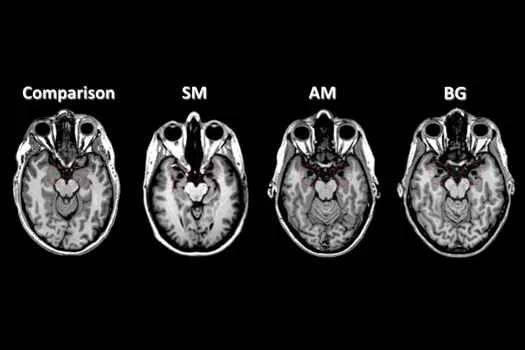

「我們可以確定——而且我們基本上已經做到了——人腦的哪些部分對我們所擁有的意識類型至關重要,並看看這些部分在殭屍身上是否完好無損,」蘇塞克斯大學薩克勒意識科學中心的科學家丹尼爾·博爾說。 “前提是我們能把殭屍放進腦部掃描儀裡。”

例如,如果我們發現殭屍大腦中沒有丘腦,科學家就會一致認為殭屍可能沒有意識。如果殭屍大腦各區域之間存在許多複雜的相互作用,那就意味著它們擁有高度的意識。